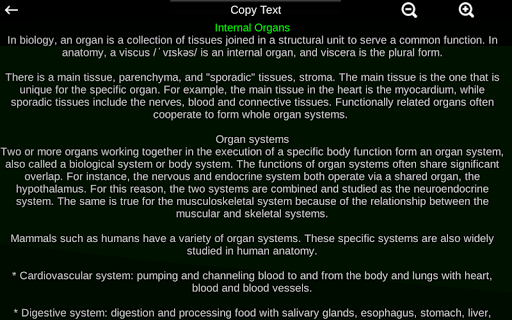

* Описи кожного органу.

Ця програма розроблена, щоб доповнити вивчення анатомії в різних освітніх, медичних і культурних умовах.

Практична, корисна та цінна анатомічна інформація у вас під рукою.